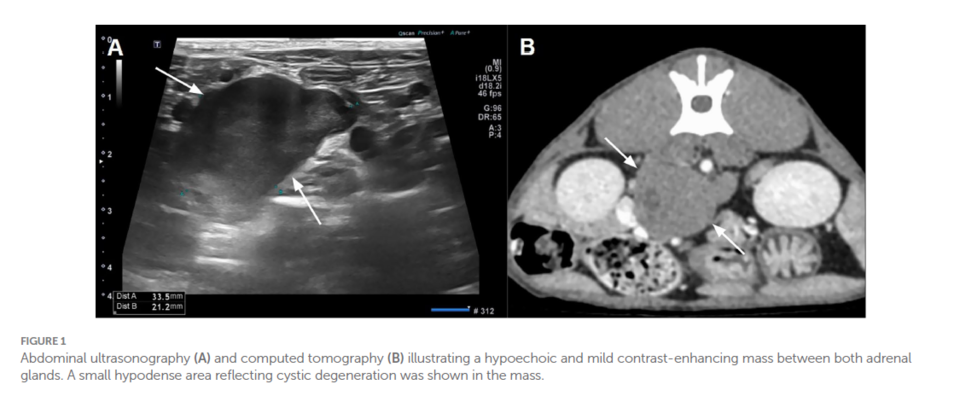

이번 연구는 젊은 고양이에서 발생한 매우 드문 종양인 ‘부신경절종(extra-adrenal retroperitoneal paraganglioma, EAP)’을 보고한 사례다. 이 종양은 임상증상이 거의 없어 조기 발견이 어렵고, 기존에 흔히 의심되는 림프종과 구분이 필요하다.

연구팀은 조직병리학 및 면역조직화학검사를 통해 종양을 정확히 진단하고, 이를 통해 젊은 고양이에서도 부신경절종이 발생할 수 있음을 규명했다.